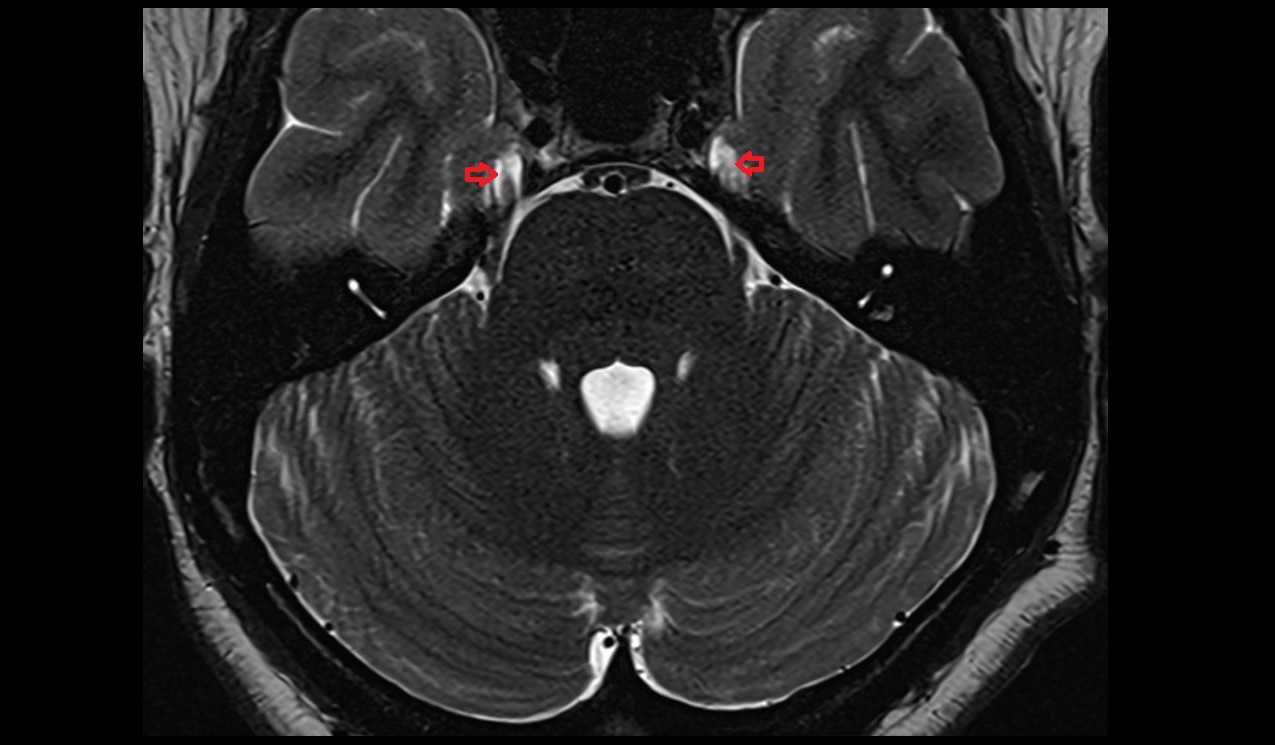

- Lateral aperture of fourth ventricle (foramen of Luschka)